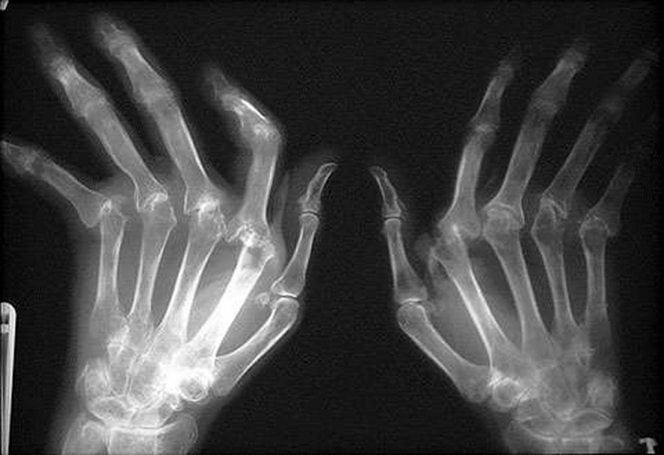

Пациентам обязательно назначается рентгенография. На полученных изображениях обнаруживаются сужение суставных щелей, диффузный или пятнистый эпифизарный остеопороз, множественные или единичные краевые эрозии.